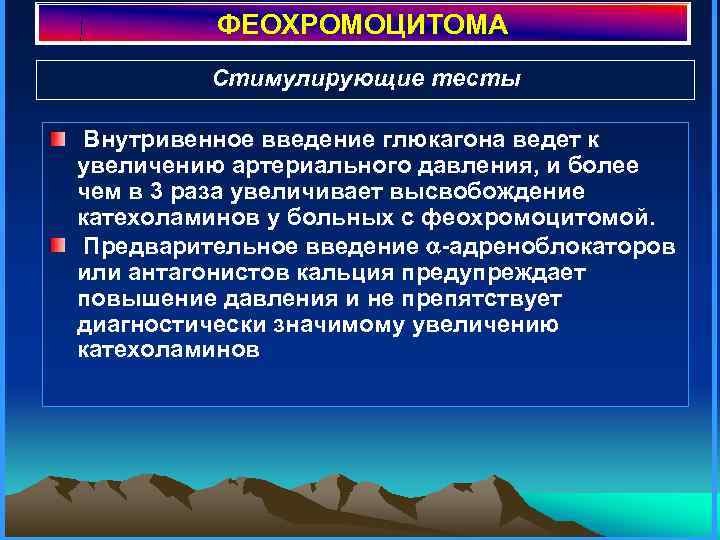

ФЕОХРОМОЦИТОМА Стимулирующие тесты Внутривенное введение глюкагона ведет к увеличению артериального давления, и более чем в 3 раза увеличивает высвобождение катехоламинов у больных с феохромоцитомой. Предварительное введение -адреноблокаторов или антагонистов кальция предупреждает повышение давления и не препятствует диагностически значимому увеличению катехоламинов

ФЕОХРОМОЦИТОМА Стимулирующие тесты Внутривенное введение глюкагона ведет к увеличению артериального давления, и более чем в 3 раза увеличивает высвобождение катехоламинов у больных с феохромоцитомой. Предварительное введение -адреноблокаторов или антагонистов кальция предупреждает повышение давления и не препятствует диагностически значимому увеличению катехоламинов